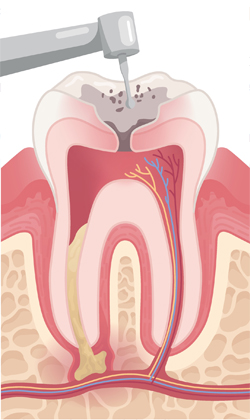

치아 윗부분에 작은 구멍을 만들어 신경관으로 진입할 길을 마련합니다. 이를 통해 내부 염증 부위를 정확히 확인할 수 있습니다.

염증이 생긴 신경과 감염된 조직을 제거하고, 뿌리관 내부를 깨끗하게 청소한 뒤 치료에 적합하도록 넓히고 정돈합니다.